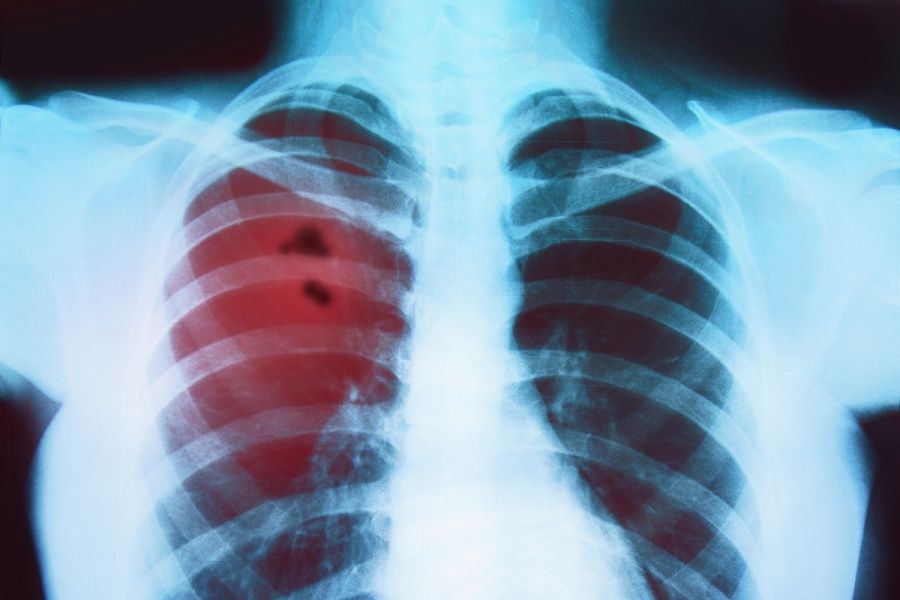

Das radioaktive Element Polonium-210 ist in der Tabakpflanze enthalten. Über ein Jahr hinweg entsprechen 20 bis 40 Zigaretten pro Tag 250 mal Lungenröntgen. Das Metall Cadmium wird nicht nur als Halbleiter in Handyakkus verwendet, auch die Tabakpflanze ist ein absoluter Cadmiumsammler.